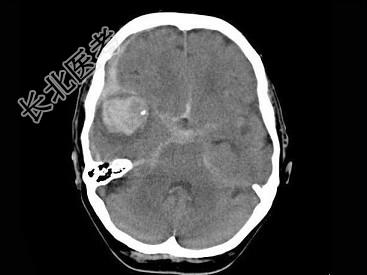

- 单项选择题女,79岁, 步行时突然摔倒,结合图像, 最可能的诊断是 ( )

A、右大脑中动脉破裂出血

B、脑转移瘤出血

C、脑膜炎

D、脑梗死

E、脑脓肿